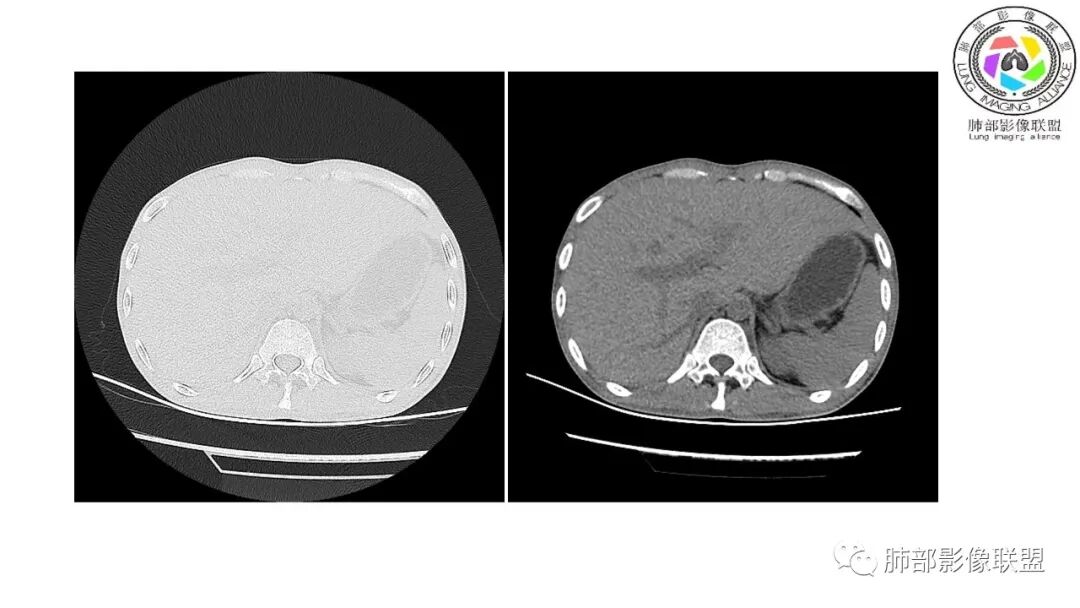

以下为2021-7-15日上腹部CT

影像与临床:1.青年男性,HlV阳性,颜面部皮疹(未提供皮疹图像)、发热(高热),实验室CRP、PCT高,T-Spot阴性。2.右肺下叶空洞结节,壁厚不均,边界清楚,其内线状影,未见液平及钙化,未见卫星灶,纵隔淋巴结增大,双侧腋窝见增大淋巴结。心腔内低密度提示贫血可能。肝脾影增大,未见结节影及块影。腹膜后见多发增大淋巴结。